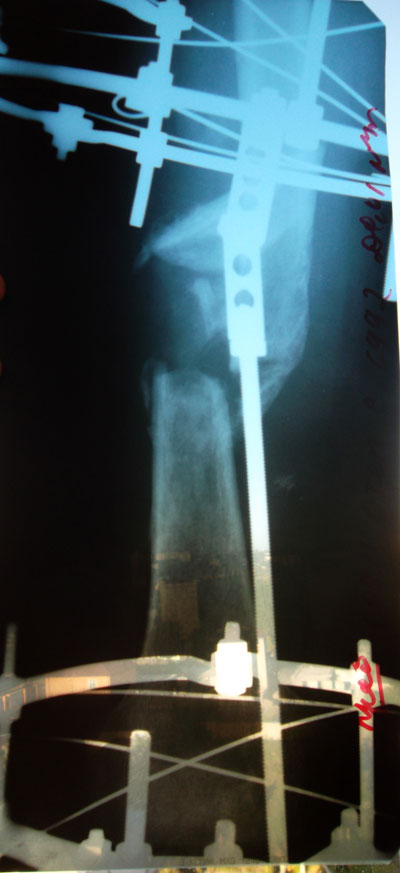

Сегодня, 14.12.2011, сняли мой аппарат. Результат вы видите на фото. Большое спасибо Н.Н.Онипко, очень рад что попал в эти руки. Эти 3,5 месяца прошли как сон, сейчас смотрю и думаю, как будто никакого аппарата и не было на моей ноге. Интересно. Будто никогда не ломал ногу, будто все это был сон. В...

Сегодня распустили болты аппарата. В понедельник уже снимут аппарат. Ровно 3,5 месяца ходил. Никаких проблем не возникло в течений этого времени. Никаких боли не было. Кости хорошо срослись. Все отлично!

Ноги выровнены полностью, стою на фиксации.

Укорочение устранено, осталось убрать наружную ротацию. Доктор сказал, что на днях аппарат уменьшится в два раза. Хочется верить! :)

Сейчас я в аппарате Илизарова-Онипко.

Укорочение бедра на 5 см устранено. Дистракция в день 6 мм.